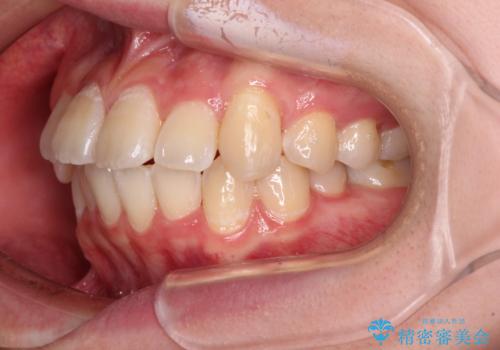

【モニター】八重歯と前歯のクロスバイト ワイヤーを併用しインビザラインで矯正治療

- 前歯のデコボコと八重歯を気にして来院された患者様です。

インビザラインでの治療を希望されていましたが、前歯のクロスバイトや下顎小臼歯の捻転が認められたため、インビザライン単独で治療を行うよりも、ワイヤー装置を併用した方が、治療期間の短縮やトラブル回避できると判断し、ワイヤー装置を併用することとしました。

まずはワイヤー装置により前歯のクロスバイトと下顎小臼歯の捻転を改善し、その後インビザラインにより全体を整える矯正治療を行うこととしました。